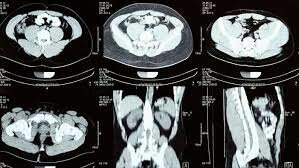

• 1989- 2004 Escáner espiral de múltiples rebanadas

1989- 2004 Escáner espiral de múltiples rebanadas

Es la combinación del haz en forma de cono deslizándose muy rápido para adquirir imágenes